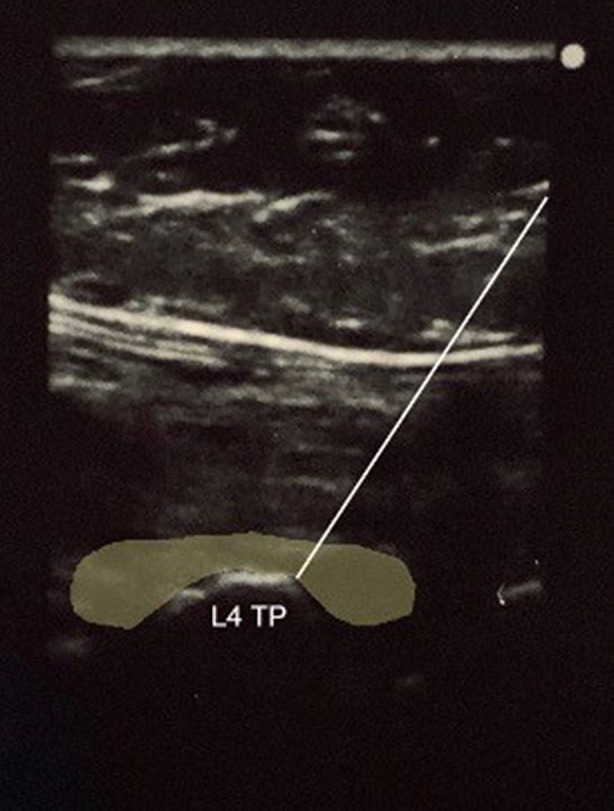

Standard technique for the ESPB was performed by the lead investigator. With the cadaver in prone position, a Sonosite M-Turbo (Sonosite Inc., Bothell, WA, USA) ultrasound machine with a high-frequency linear transducer (13–6 MHz) was used to longitudinally scan and identify the sacrum and then moved cephalad to identify the spinous process of L4. The transducer was then moved laterally until the transverse process of L4 with overlying erector spinae muscle plane was identified. A 9 cm, 21 G needle (Arrow StimuQuik ECHO Stimulating and Echogenic Peripheral Nerve Block Needle) was inserted in-plane in a caudocranial direction until it was visualized contacting the dorsal surface of the transverse process of L4. A solution consisting of 1 ml of methylene blue and 19 ml of 0.25% bupivacaine was used to more closely approximate injectate used during ESPBs. The 20 ml solution was slowly injected, over approximately 30 s, under direct ultrasound visualization to confirm spread deep to the erector spinae muscle fascial plane (Fig. 1). The procedure was then repeated on the contralateral side.

Fig. 1.

In-plane ultrasound-guided erector spinae plane block at the transverse process of L4 with highlighted area of injectate spread

A bilateral L4 ESPB was successfully performed at L4 in a single cadaver model. Appropriate craniocaudal injectate spread in the plane deep to the lumbar erector spinae muscles was observed using ultrasound (Fig. 1). After posteroanterior plane dissection, the injectate solution was observed to have spread in a craniocaudal direction consistently extending from L2 to the sacrum, bilaterally (Fig. 2). Staining from the methylene blue was found dorsal to the transverse processes at these levels and extending to the inside of the erector spinae muscles, covering the posterior rami. Dissection deep to the erector spinae showed that the dye did not reach the ventral rami of the spinal nerves (Fig. 3). There was no dye present in the subcutaneous layer other than trivial leakage that likely occurred during needle placement. No laminectomy was performed and the epidural space was not dissected.